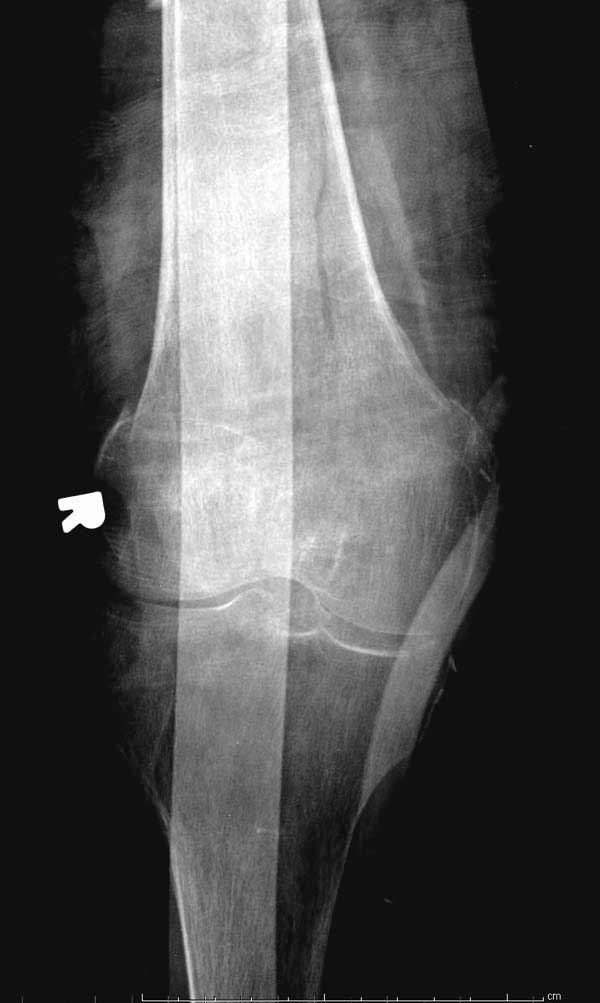

Первые снимки показывают технические погрешности установки DHS. Не была достигнута репозиция, конечность в флексии и шейка в ротации. Сегодня все меньше обращают внимание на параметры для оценки репозиции (S контуры Lowell в обеих проекциях и Garden Alignment Index, в норме 155 и 180 градусов), хотя такие простые тесты помогли бы дорепонировать смещение. Винт находится сзади в головке, что при нагрузке поменяет вектор и вместо компрессии в линии перелома срежет головку-Cut Out!

В зависимости от дистанции линии перелома и латерального кортекса надо использовать разной длины barrel, т.е. конец баррели не должен доходить до пределов перелома. Здесь конец длинного ствола упирается в медиальный фрагмент, что мешает созданию компрессии, а более короткий barrel создал бы запас для компрессии. В боковой пластине вместо 4х можно было ограничится двумя шурупами, потому что головка шурупа в 4.5 мм выдерживает давление до 350 кг.